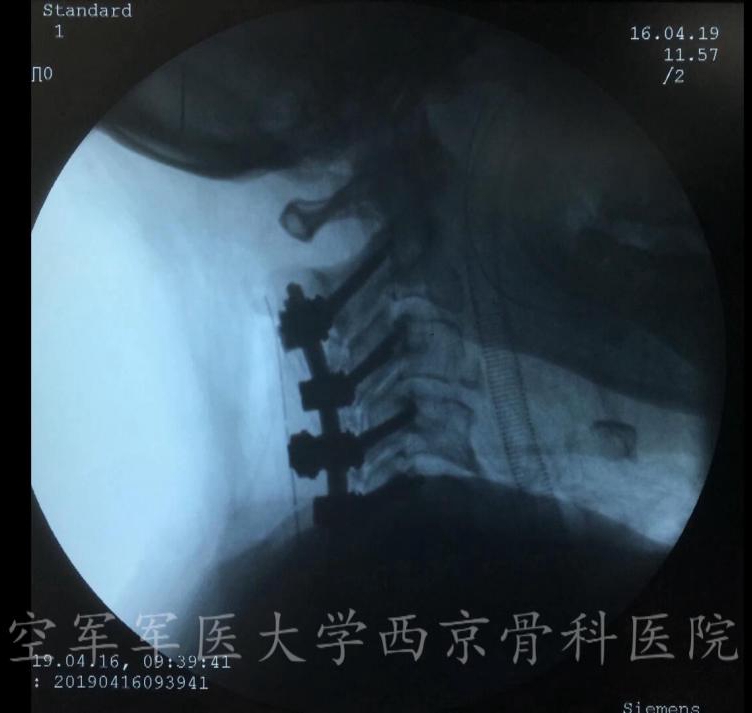

术中完成减压后置入钉棒系统

术中C臂透视